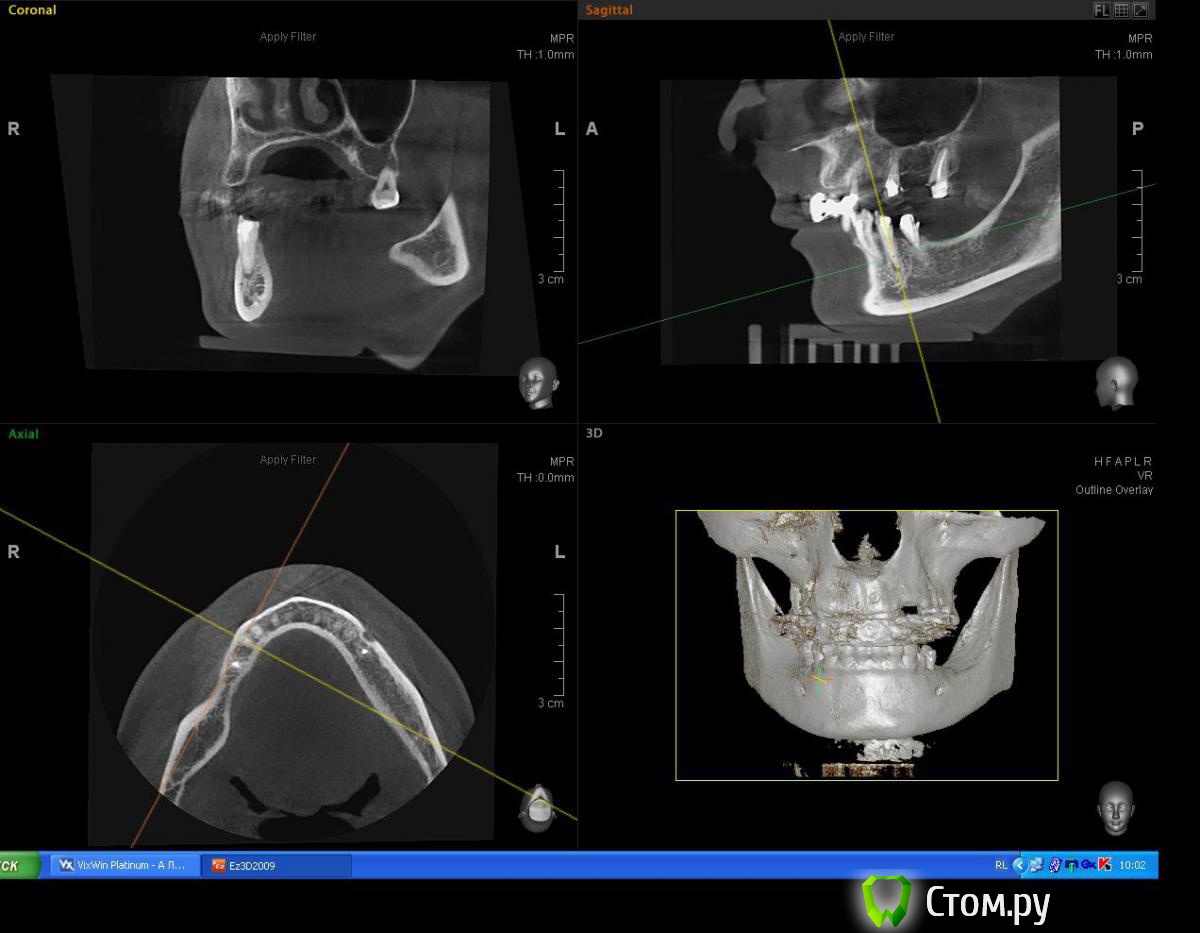

Mane Опубликовано 2 июля, 2014 Поделиться Опубликовано 2 июля, 2014 Для первичной фиксации вам неоходимо хотя бы 3-4 мм нативной кости в заапекальном направлении. Судя по срезам, они имеются, однако вместе со срезами лучше делать промеры (длина, ширина, толщина) для полноценной идентификации. Так же можете создать вируальный имплантат с планируемыми размерами и оценить его положение на срезах. +1 скорее всего вам будет достаточно 38х10 3 Ссылка на комментарий

Евгений Ходыкин Опубликовано 2 июля, 2014 Автор Поделиться Опубликовано 2 июля, 2014 Замеры по 4.4 зубу: Ссылка на комментарий

Евгений Ходыкин Опубликовано 2 июля, 2014 Автор Поделиться Опубликовано 2 июля, 2014 Замеры по 3.4 зубу. Срезы с одним замером - это внутрикостная длина корня зуба. Ссылка на комментарий